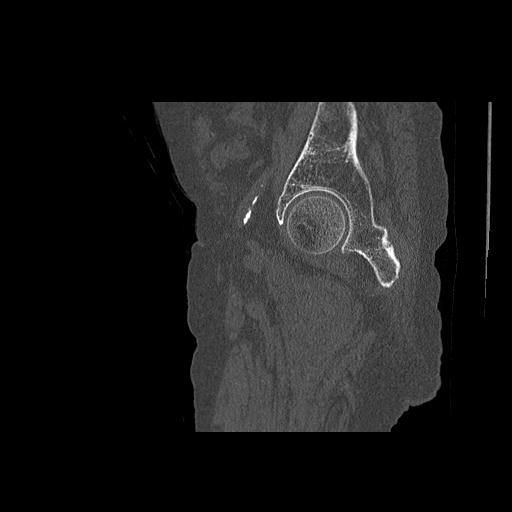

102803 1/12(キウスなし) 1/27 左下腿 4R 30歳女性 左脛骨軸内釘